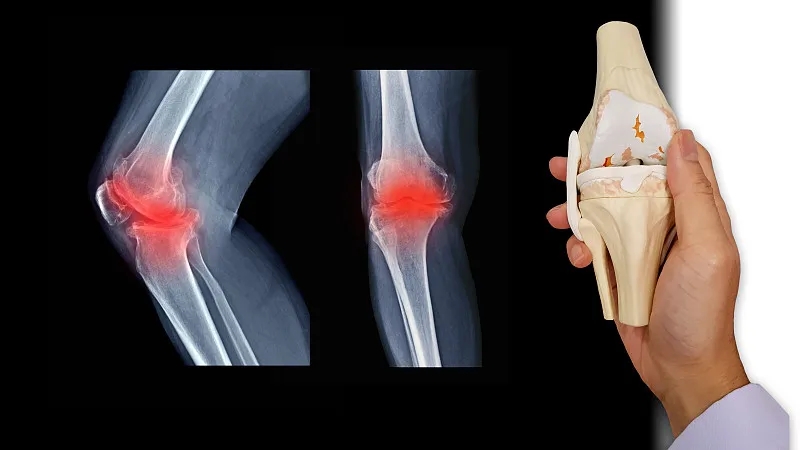

關節炎是一個通用術語,表示關節發炎。骨關節炎,俗稱磨損性關節炎,是最常見的關節炎類型。它與關節軟骨的破壞有關,并且幾乎可以發生在身體的任何關節中。它通常發生在臀部、膝蓋和脊柱的負重關節中。它還會影響手指、拇指、頸部和大腳趾。

軟骨是一種堅硬的橡膠狀材料,覆蓋在正常關節的骨骼末端。它的主要功能是減少關節處的摩擦,起到“減震器”的作用。正常軟骨的減震特性來自其在受壓(壓平或壓在一起)時改變形狀的能力。

骨關節炎導致關節中的軟骨變硬并失去彈性,使其更容易受到損傷。隨著時間的推移,軟骨可能會在某些區域磨損,從而大大降低其作為減震器的能力。隨著軟骨退化,肌腱和韌帶伸展,引起疼痛。如果情況惡化,骨頭可能會相互摩擦。

您的醫生可能會使用X光檢查來幫助確認診斷并確保您沒有其他類型的關節炎。X 射線顯示發生了多少關節損傷。如果X射線結果不能明確指出關節炎或其他疾病,則可能需要進行MRI以更好地觀察關節和周圍組織。